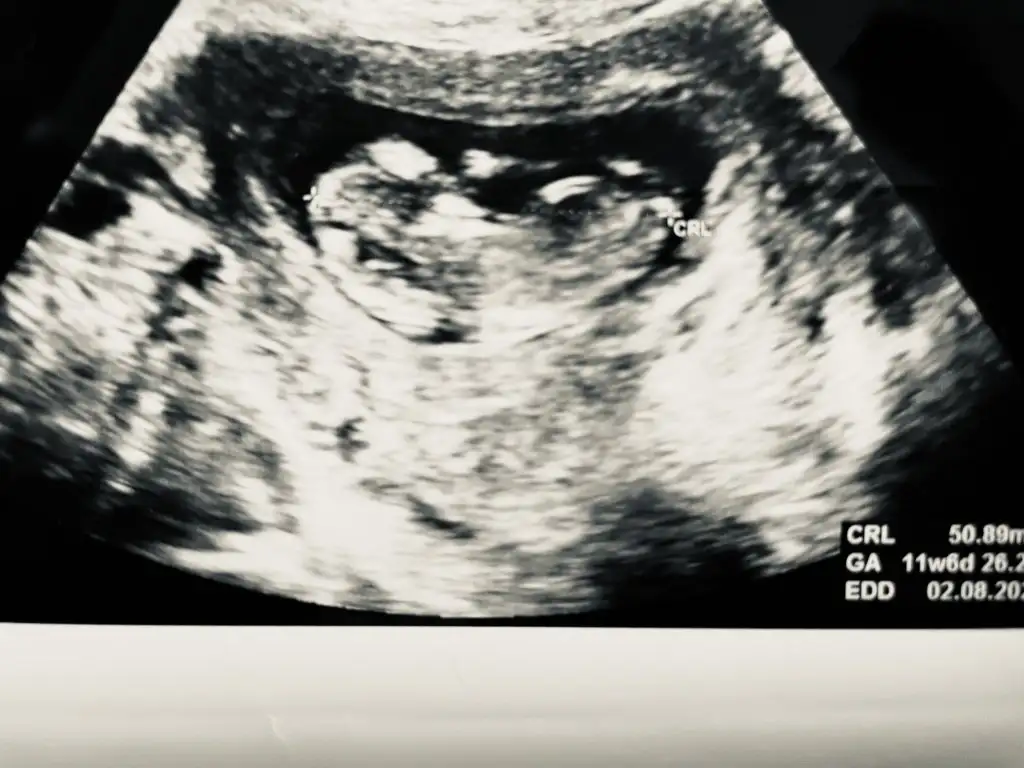

Banada yorum yaparmisiniz 13+1

Eklentiler

• IMG_20220121_090903_BURST001_COVER.webp

IMG_20220121_090903_BURST001_COVER.webp

22,4 KB · Görüntüleme: 52